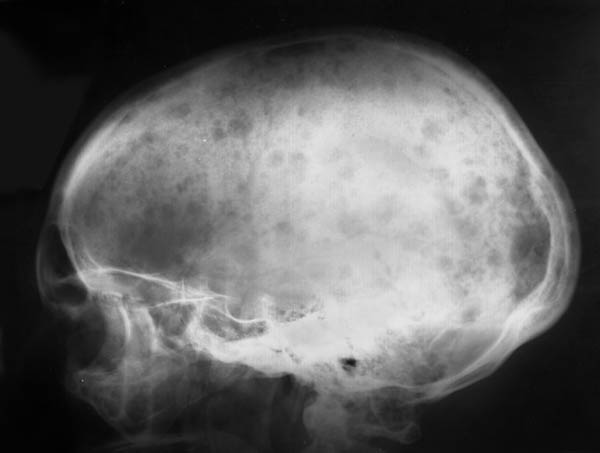

Инструментальные и лабораторные признаки патологии костей черепа

Основным методом диагностики остеопороза, независимо от его локализации, является рентгенография. Однако этот метод имеет ограниченную информативность и служит лишь первым шагом в обследовании при подозрении на заболевание. Рентген не позволяет точно оценить степень потери костной массы.

Симптомы остеопороза спинки турецкого седла и других костей черепа

Клинически остеопороз может не проявляться. Симптомы часто связаны с увеличением размеров аденомы гипофиза, что приводит к сжатию спинки турецкого седла и других костей черепа. У пациента могут возникать интенсивные и постоянные головные боли, а также нарушения зрения. Если опухоль вызывает повышенную выработку тиреотропного гормона, симптомы будут зависеть от гиперфункции щитовидной железы.

В некоторых случаях остеопороз спинки турецкого седла может быть вызван злокачественной артериальной гипертензией. Это состояние приводит к отеку тканей головного мозга, что вызывает значительное давление на костные структуры черепа, включая спинку турецкого седла. В результате происходит истончение кости и снижение минеральной плотности. Основные признаки включают симптомы отека мозга, такие как тошнота, рвота и сильные головные боли.

Диагноз остеопороза часто устанавливается случайно, когда проявляются симптомы основного заболевания, вызвавшего его развитие. Исключение составляют переломы костей черепа, которые являются серьезным осложнением остеопороза. Это происходит из-за хрупкости костей, вызванной недостатком минеральных веществ, таких как кальций и витамин D.